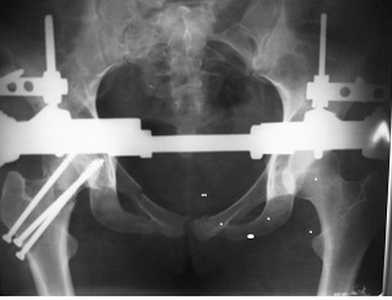

[Ortho] перелом костей таза

У нас был такой случай, прооперировал на 3 сутки. Результат полное выздоровление.

Имя     : Таз и шейка письмо.jpg